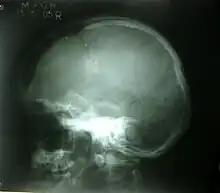

Diastatic

Diastatic fractures occur when the fracture line transverses one or more sutures of the skull causing a widening of the suture. While this type of fracture is usually seen in infants and young children as the sutures are not yet fused it can also occur in adults. When a diastatic fracture occurs in adults it usually affects the lambdoidal suture as this suture does not fully fuse in adults until about the age of 60. Most adult diastatic fractures are caused by severe head injuries. Due to the trauma, diastatic fracture occurs with the collapse of the surrounding head bones. It crushes the delicate tissue, similarly to a depressed skull fracture.

Diastatic fractures can occur with different types of fractures and it is also possible for diastasis of the cranial sutures to occur without a concomitant fracture. Sutural diastasis may also occur in various congenital disorders such as cleidocranial dysplasia and osteogenesis imperfecta.[4][5][6][7]